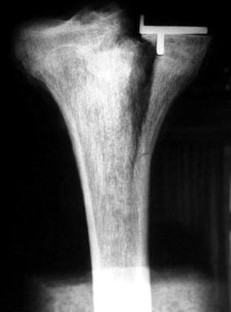

Tibial components of the Oxford Uni were implanted in six paired fresh-frozen tibiae with a defined extended saw cut (10°) at the dorsal cortex of each specimen. In one set, surgery was performed with cement fixation, and in the other, cementless components were implanted. Vertical loads were then applied under standardised conditions to fracture the specimens.

Fig. 1